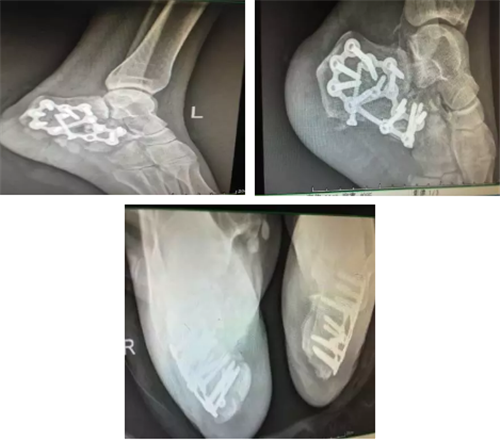

| 2017年11月20日,郴州市第四人民医院骨科主任谭宜昌带领其团队应用3D打印技术成功为一双侧跟骨粉碎性骨折患者实施了手术,术后患者恢复良好。 该患者为一年轻女性,自高处坠落导致双侧跟骨粉碎性骨折,骨折移位较大,为复杂型骨折。对于该疾病使用过去传统影像学方法难以直观了解骨折情况,尤其是年轻医生较难准确对骨折进行评估和分型。模拟手术多在二维图纸或者术者的脑海中进行,在实际手术操作中也只能凭经验进行操作,凭经验选择置入物的规格,并现场将置入物进行折弯、剪裁,调整成较为合适的尺寸。且螺钉方向也只能依靠医生的解剖知识及经验进行确定。这种经验性手术操作准确性较差,过程复杂,耗时长,透视多,创伤大。 而通过3D打印技术将患者术前跟骨CT平扫加三维重建产生的DICOM数据经计算机处理,修改后获得打印模型的标准格式数据,连接3D打印机,根据需要选择不同类型的3D打印技术进行三维物理模型打印。利用该项技术打印出来的骨折模型非常准确,为患者和医生提供了较为直观的触觉与视觉上的体验,能提高医生与患者及家属交流的效果,能为手术方案的设计和制定以及术前演练提供有力的参数和依据,需要多长的钢板,需要几颗螺钉,医生在术前就能心中有数。这不仅大大提高了手术的精确度,提高手术效果,而且还能有效减小创伤,减少术中出血,节省手术时间,缩短患者术后恢复时间,为患者节省医疗费用。

术前CT扫描

术后X线